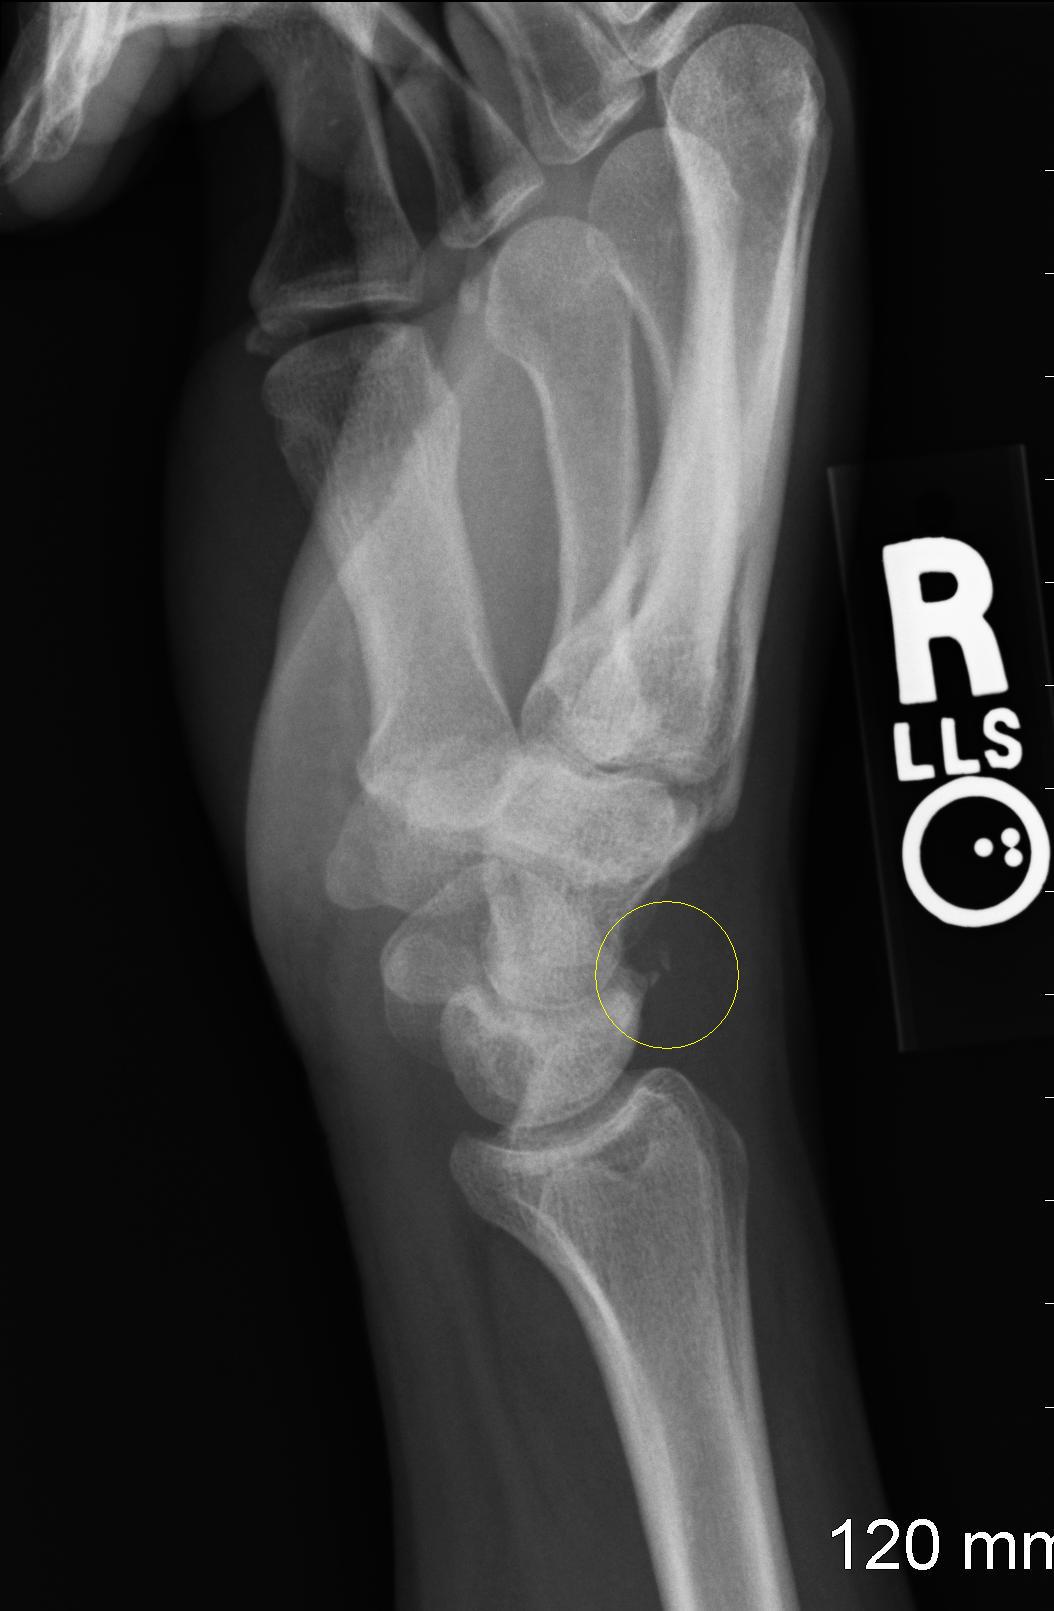

El primer paso crítico en el tratamiento de traumatismos faciales es la evaluación inicial por parte de traumatólogos en Monterrey. Este proceso incluye una revisión minuciosa de la historia clínica del paciente, exámenes físicos detallados y, en muchos casos, estudios de imágenes como radiografías o tomografías computarizadas. La precisión en el diagnóstico es esencial para diseñar un plan de tratamiento efectivo.